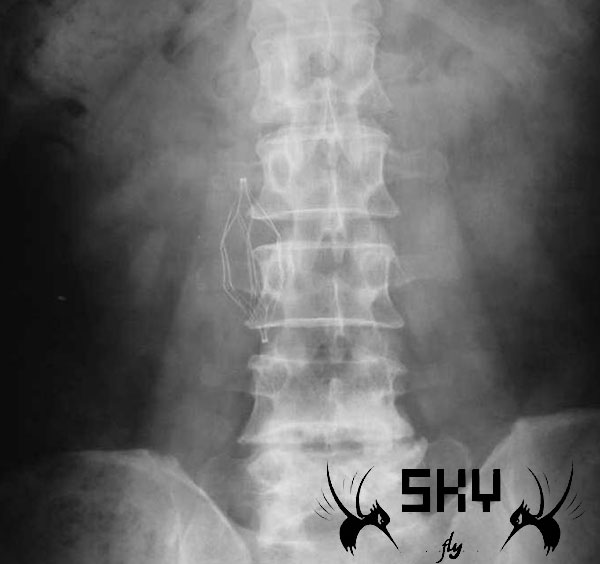

下腔静脉滤器对于大家来说并不陌生,在这里和大家分享一个下腔静脉滤器的释放和取出的操作视频,希望对大家有所裨益。视频播放密码为sky